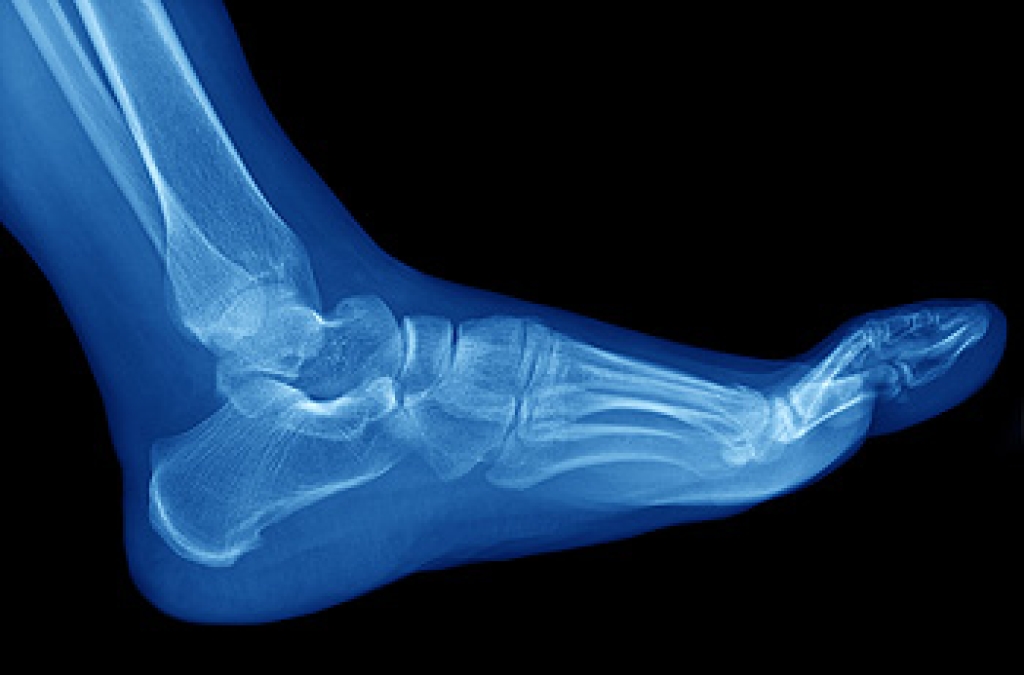

Stress fractures in the feet are a common injury, particularly among athletes. They can be caused by any activity that puts increased pressure on the feet, from playing a high impact sport to starting a new workout routine. A sudden increase in activity, for example, running for much longer than usual, can overload the bones in your feet. Changing the surface that you train on can have a similar effect, specifically if you are moving from a soft surface, like turf, to a hard one like asphalt. Having an improper running technique or wearing the wrong shoes can also lead to stress fractures. If you are suffering from any type of foot pain, please seek the care of a podiatrist.

Stress fractures occur when there is a tiny crack within a bone. To learn more, contact one of our podiatrists from APEX Foot & Ankle Center. Our doctors can provide the care you need to keep you pain free and on your feet.

Stress fractures are the result of repetitive force being placed on the bone. Since the lower leg and feet often carry most of the body’s weight, stress fractures are likely to occur in these areas. If you rush into a new exercise, you are more likely to develop a stress fracture since you are starting too much, too soon. Pain resulting from stress fractures may go unnoticed at first, however it may start to worsen over time.